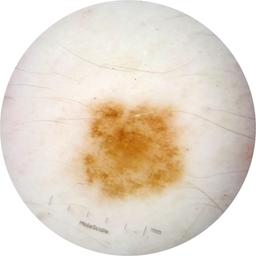

ISIC_9219276

Clinical

Field Value

acquisition_day 482

age_approx 55

anatom_site_1 Trunk

anatom_site_2 Posterior trunk

anatom_site_general posterior torso

concomitant_biopsy False

diagnosis_1 Benign

diagnosis_confirm_type single image expert consensus

family_hx_mm True

image_manipulation instrument only

image_type dermoscopic

lesion_id IL_5010026

patient_id IP_7167913

personal_hx_mm True

sex male